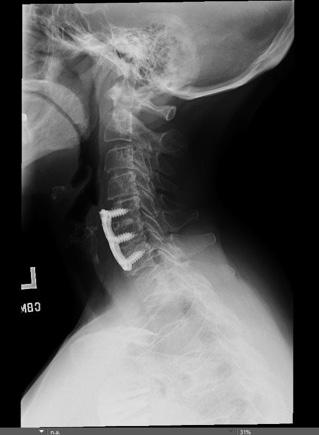

Figure 1. 40-year-old orthopedic spine surgeon with cervical radiculopathy involving the left upper extremity, resulting in sleep disturbance and eventual cervical disc replacement. The surgeon required time away from operative practice for recovery.

for magnification yet require frequent neck flexion. A prolonged downward gaze during loupe use may increase cervical loading and lead to further neck strain.7-9 Biomechanical analysis demonstrates that cervical flexion significantly increases mechanical load on the cervical spine. When the head is held in a neutral position, the cervical spine supports approximately 10–12 lb of load, whereas 30° of flexion increases this load to ~40 lb and 60° of flexion increases it to ~60 lb, illustrating how prolonged downward gaze during loupe use can substantially increase cervical strain during operative procedures. 5 Being mindful of neck extension and flexion while wearing loupes is a small adaptation that surgeons should use to minimize the strain on the cervical spine. 5,6 To aid in decreasing strain, a newer prismatic loupe has been designed aimed at promoting a neutral and aligned head position.